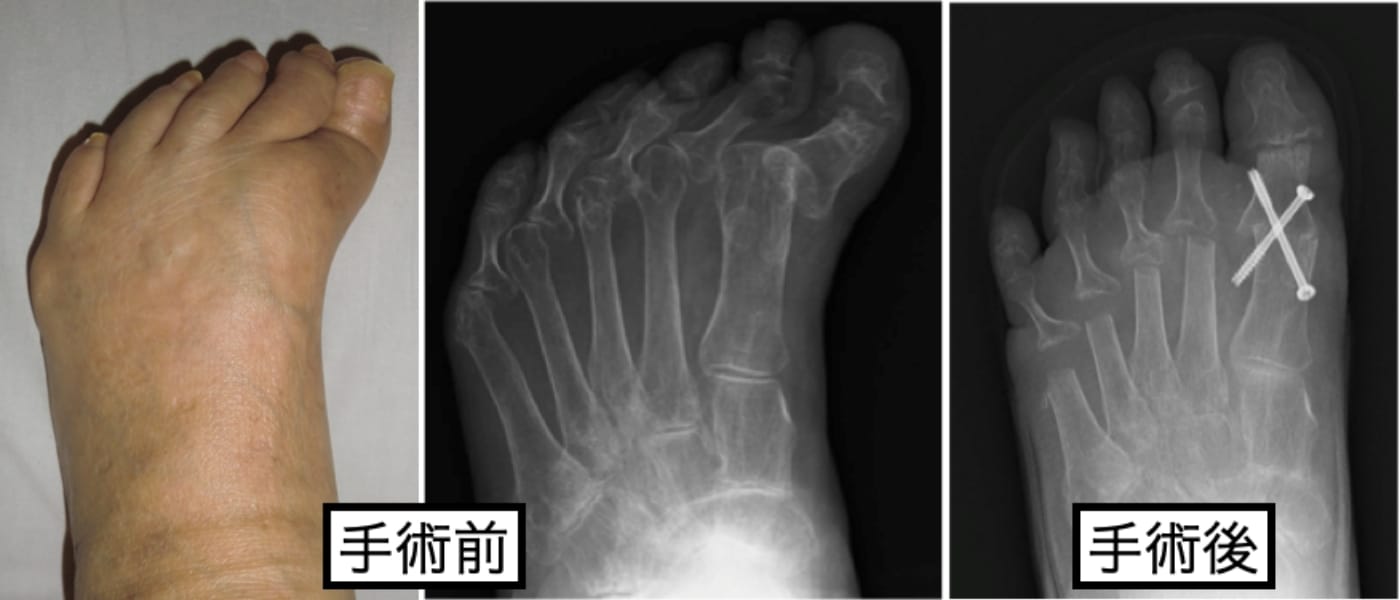

当科では、関節リウマチによる前足部変形に対して、従来行われていた第1MTP関節固定術と第2〜5中足骨頭切除による切除関節形成術を組み合わせた足趾形成術も行なっております(下図)が

抗リウマチ治療により、疾患活動性が落ち着いている場合や足趾関節の破壊が高度でなければ、可能な限り関節温存型の足趾形成術を行なっています(下図)。

足趾関節を温存することで、足部の踏み返し運動の改善が期待できるため、歩容の改善も期待できます。また、中足骨頭を残す際に骨頭の配列も矯正するため、足底部の有痛性胼胝の自然軽快も期待できます(下図)。